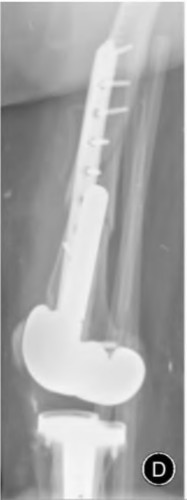

Question 68

A 78-year-old female sustains a periprosthetic femur fracture 10 years after a cemented THA. Radiographs show a fracture around the tip of the stem with a loose femoral component and poor proximal bone stock, but adequate diaphyseal bone.

What is the most appropriate surgical treatment?

Explanation